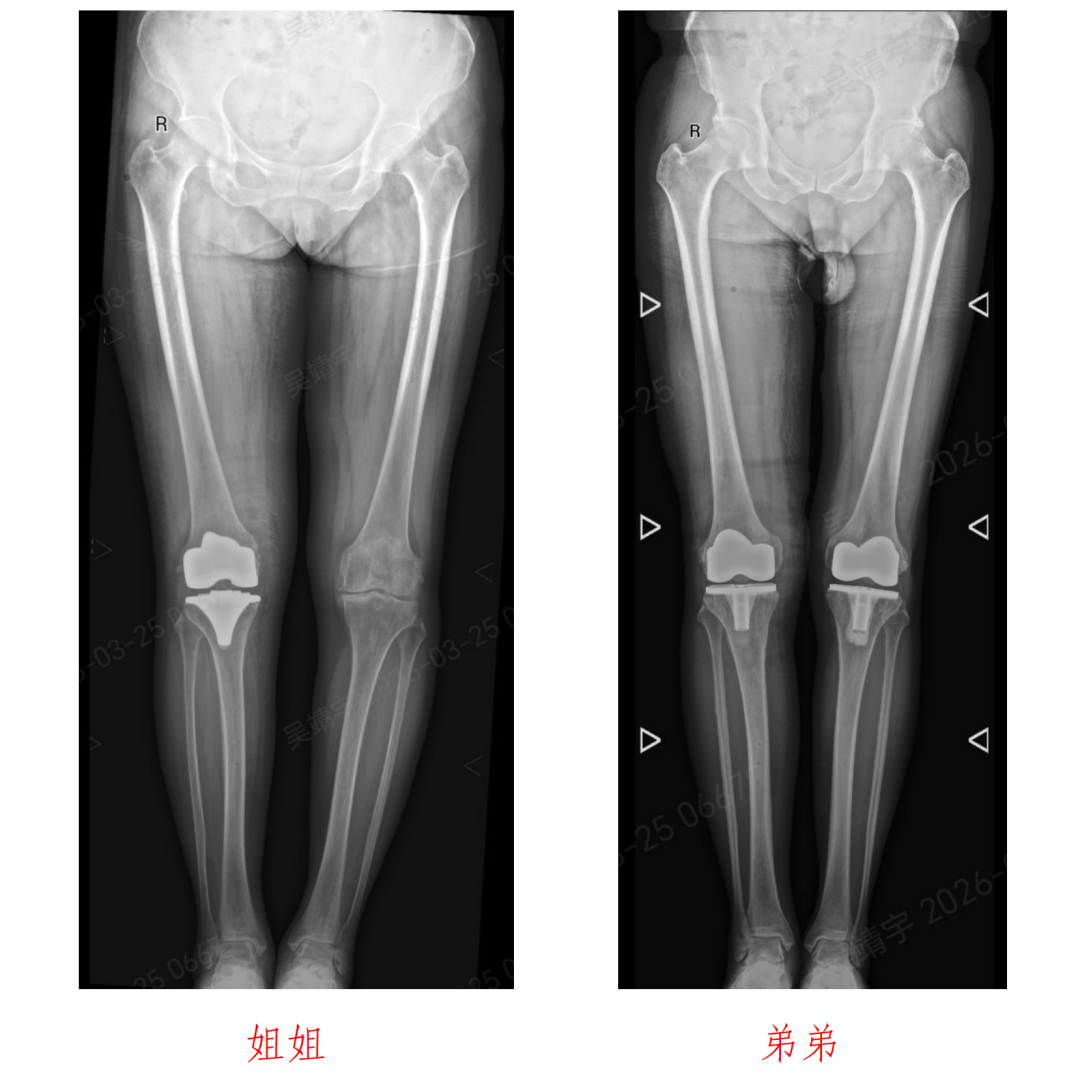

72岁的姐姐沙女士与64岁的弟弟沙先生,多年饱受膝关节病痛困扰。

近日,成人ai 关节外科主任杨锴、副主任医师吴靖宇采用骨科手术机器人辅助全膝关节置换术,成功为这对姐弟患者实施右侧人工全膝关节置换手术。

术后一周,姐弟二人膝关节功能恢复良好,疼痛症状显著缓解,均可自主下床活动,诊疗效果获得患者认可。

沙女士姐弟二人多年来均被严重的膝关节骨性关节炎困扰,膝关节疼痛、肿胀、活动受限,日常行走、上下楼梯都十分困难,严重影响生活质量。随着年龄增长,病情愈发严重,保守治疗早已无法缓解症状,都希望可以使用手术改善生活质量。

手术过程十分顺利,姐弟二人的右侧全膝关节置换手术均圆满完成。术后,医院快速康复(ERAS)护理团队同步介入,为姐弟俩制定专属康复计划,开展个性化功能锻炼指导、疼痛管理、营养支持等全方位护理。